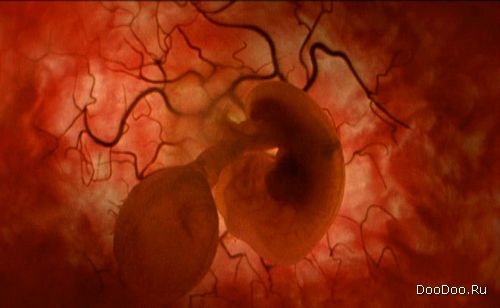

Восемь недель. Этот зародыш в состоянии пинаться и двигать ручками вверх и вниз.

Зародыш мягко перемещается в матке.